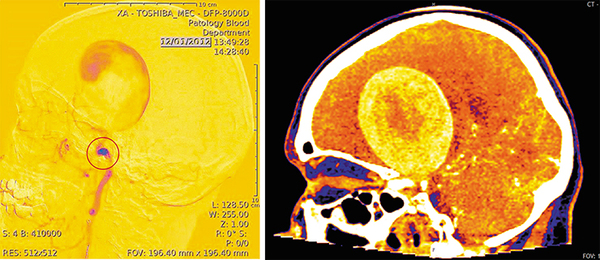

Слева: Артериальная аневризма (АА) – выпячивание стенки артерии вследствие ее растяжения. Материал стенки аневризмы отличается от материала стенки здорового сосуда. Ангиограмма выполнена в ННИИПК им.акад.Е.Н. Мешалкина. Справа: гигантская артериальная аневризма, компьютерная томография